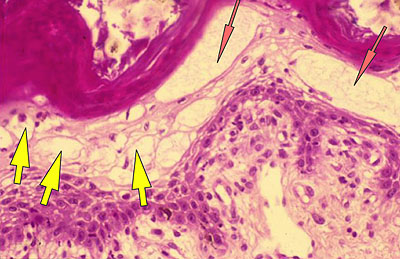

Photo 7 (Hémalun Eosine X 400) : l’aspect blanc donné par les lésions de dégénérescence balonnisante

(œdème cellulaire sévère) des acanthocytes des couches épineuse et granuleuse, qui peut être associée

multifocalement à une pycnose nucléaire (mort cellulaire) aboutissant à un aspect nécrolytique.

Légendes de la Photo 7 :

- Étoiles rouges claires : noyaux pycnotiques (acanthocytes) zones de nécrolyse épidermique

- Flèches jaune : œdème cellulaire ou dégénérescence ballonisante des acanthocytes

Photo 8 (Hémalun Eosine X 1000 objectif à immersion) : vue rapprochée des lésions

de dégénérescence balonnisante et de nécrolyse des acanthocytes de la couche épineuse.

Légendes de la Photo 8 :

- Étoiles rouges claires : noyaux pycnotiques (acanthocytes)

- Flèches jaune : œdème cellulaire ou dégénérescence ballonisante des acanthocytes

- Flèche orange :discret œdème intercellulaire (spongiose)